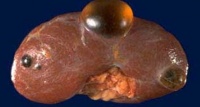

肾囊肿

肾囊肿是一种先天性遗传性疾病,肾脏实质内充满数不清大小不等的与外界不相通的圆形囊肿,囊内含有液体,小的肉眼看不到,大的可有数厘米,故称之为多囊肾。表现为夜尿增多、腰痛、高血压等。尿检有血尿、少量蛋白尿,常会缓慢地发展成为慢性肾衰。有10%的人伴有肾结石,30%的人伴有多囊肝。有经验的医生借助B超、静脉肾盂造影可确诊。

单纯性肾囊肿可能是一种先天性异常,是单侧或双侧肾及有一个或数个大小不等的圆形与外界不相通的囊腔,多数是单侧,故称单纯性肾囊肿。其发病率可随便年龄增长而增高,50岁以上的人做B超,有50%可以发现这种囊肿。借助B超、CT可确诊。

囊肿可以是一侧也可是二侧,每个肾脏有一个或少数几个囊肿。囊肿一般孤立呈球形,位于肾皮质浅表者可改变肾脏外形,也可位于皮质深层或髓质,直径0.5~1㎝,也可3~8㎝,囊壁薄而透明,内含草黄色液体,较粘稠,如有过炎症,囊壁可增厚,纤维化甚至钙化。囊肿与肾盂不相通,壁内衬以单层扁平上皮细胞。

单纯性肾囊肿常累及肾下极。出现症状的囊肿其直径平均约为10厘米,但也有少数可大至充满胁腹部。囊肿内通常含清亮琥珀色囊液。囊壁很薄,囊肿常呈“蓝色圆顶”状。偶可见囊壁钙化。约5%的囊肿含血性囊液,其中半数囊壁上可能有乳头状癌。单纯性肾囊肿好发于肾脏表面,但也可位于深部。当一囊肿位于深部时,其囊壁就与肾盂及肾盏的上皮内壁紧连,要将它们分开十分困难,但囊肿并不与肾盂相通。镜检可发现囊壁有重度的纤维变性及玻璃变性,还可见到钙化区域,邻近肾组织也受压发生纤维变性。许多发生于儿童的单纯性肾囊肿已有报道,但巨大囊肿还是罕见于儿童。此时,须先排外癌肿存在的可能。在尿路造影中,多小房性肾囊肿与肿瘤可相混淆。超声影象可以确诊,偶需行CT及MRI检查。.

肾囊肿包括单发性肾囊肿、先天性多囊肾和先天性多发性肾囊肿等。患者平时没有什么症状,仅通过B超检查发现肾脏上长一个或数个囊肿。少数人也可以长多个囊肿,但双侧同时存在囊肿者少见。这种囊肿的壁很薄,囊内为澄清带黄色的液体,囊肿大多为核桃大小。肾囊肿发生原因还不十分清楚,一般认为属于肾脏退行性变,因而发病者多为老年人。小的囊肿不会引起任何症状。近来由于B超检查的广泛开展,所以发现有肾囊肿者也增多了。